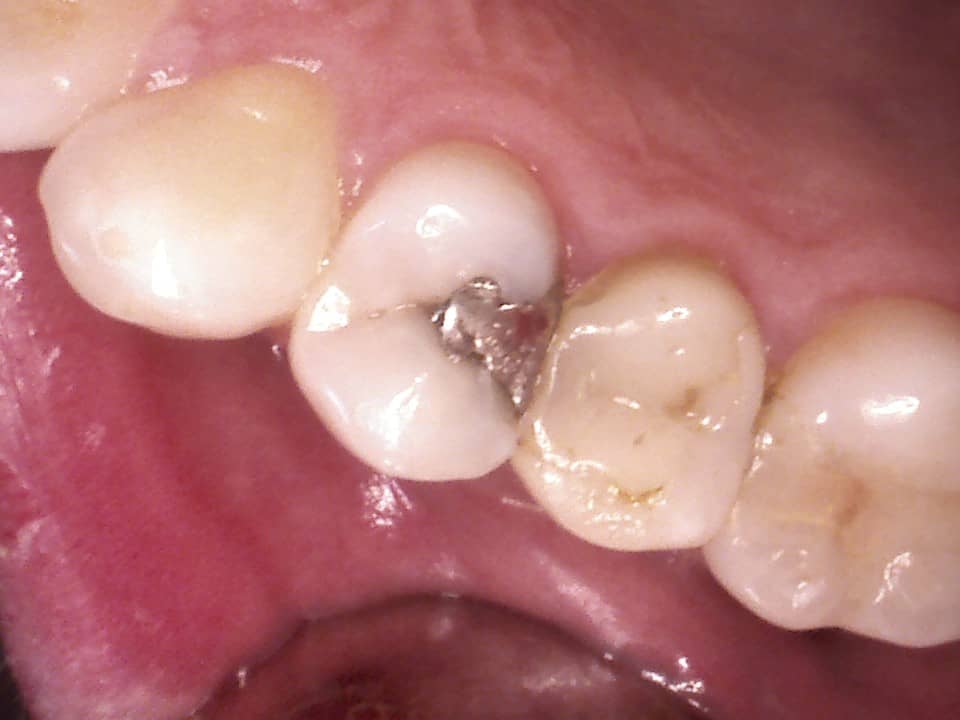

Sind Ihre Zähne doch einmal erkrankt – zum Beispiel an Karies – helfen wir Ihnen gerne, indem wir den Defekt mit Komposit- oder Amalgamfüllungen wieder reparieren.